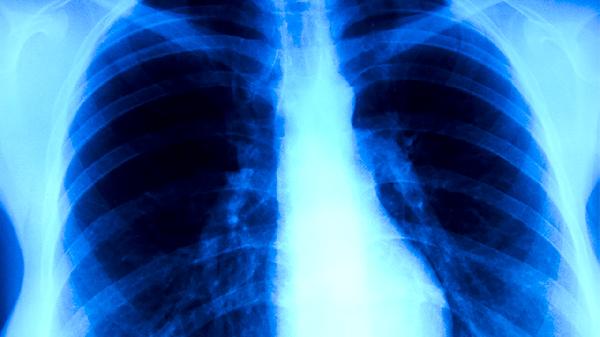

肺结核的治疗强调早期、联合、适量、规律和全程用药,具体采用口服、注射还是二者联用,必须由专科医生根据痰菌检查、药敏试验结果和影像学变化综合决定。患者切勿自行选择或更改治疗方案,应严格遵从医嘱,完成全程治疗,同时注意加强营养、保证休息、做好隔离,定期复查肝肾功能等指标,以最大程度确保疗效并减少并发症。